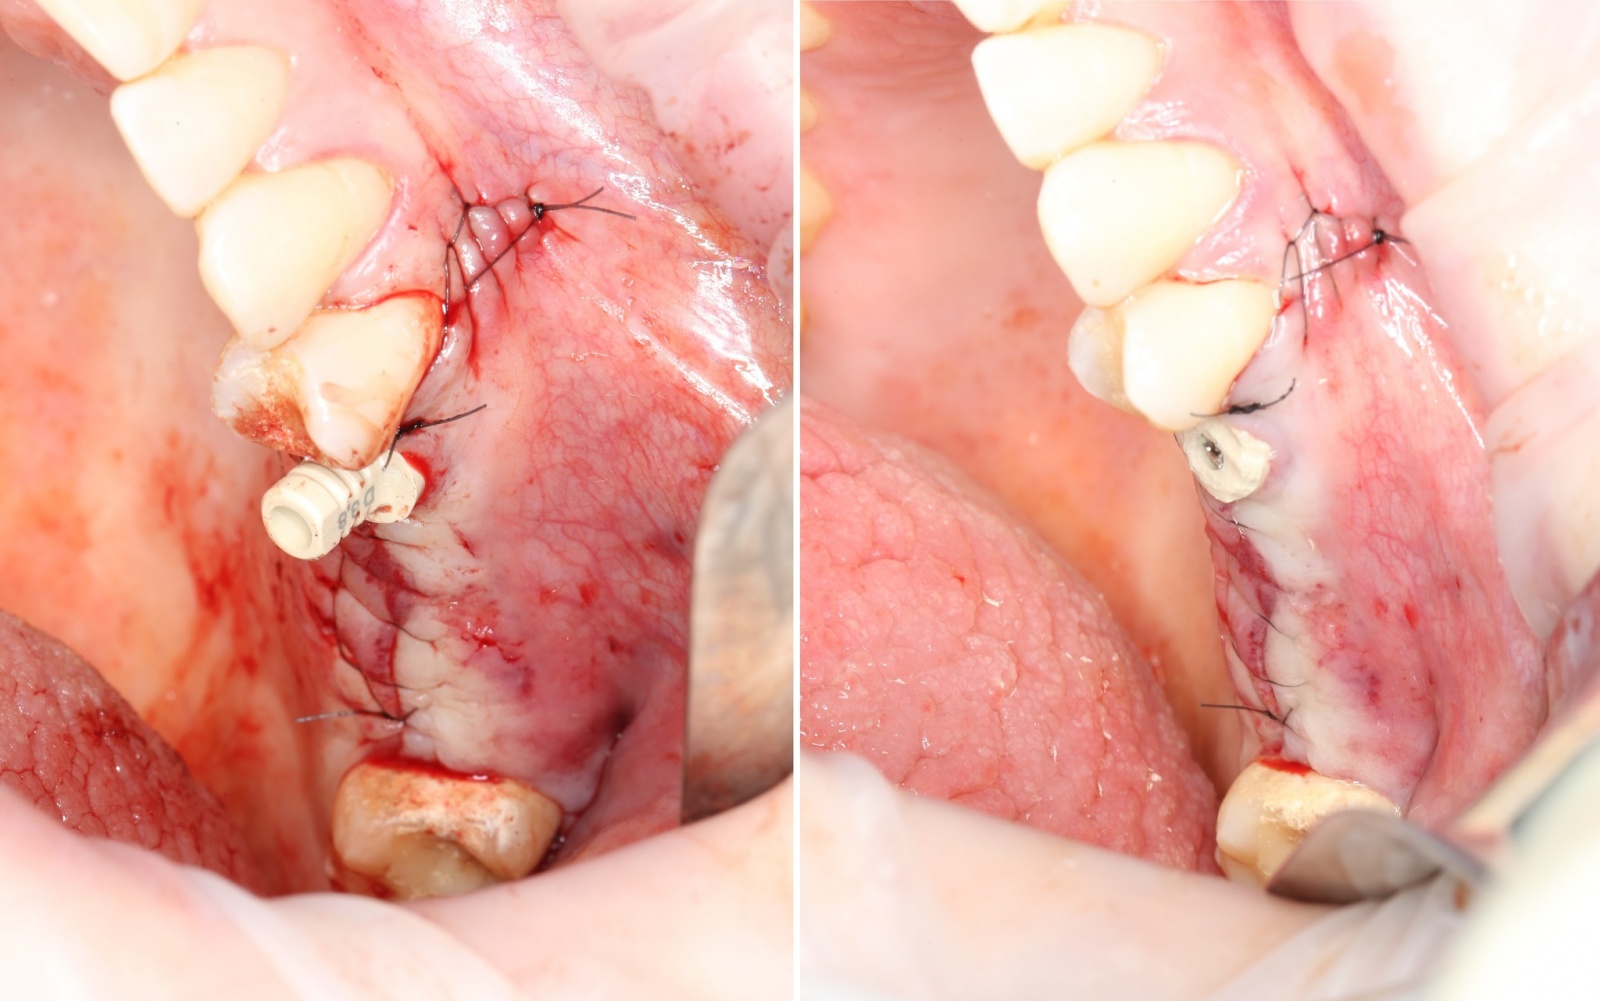

Временные абатменты меняются на заглушки:

С учётом того, что синус-лифтинг в области пятого зуба не проводился, а установленный имплантат достаточно стабилен, сразу устанавливается формирователь десны. В данном случае вместо стандартного (круглого) формирователя можно использовать Estetic cap. Его основная функция – возможность фиксации на нём временной коронки, но нам необходима лишь форма, повторяющая контуры лунки удаленного зуба.

Он фиксируется на имплантате при помощи винта:

Далее производится наложение швов (ножницы и иглодержатель):

Используется шовный материал – монофиламент (нерассасывающаяся нитка наподобие лески). В отличие от рассасывающихся швов, эта нить не скапливает на себе налет и остатки пищи, что особенно важно в случае с операциями.

Выступающую часть абатмента (он сделан из пластмассы) просто спиливаем, чтобы не мешала: